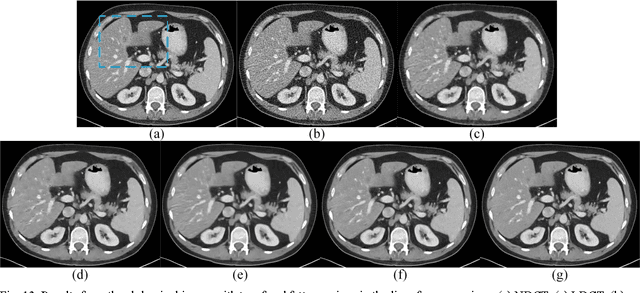

Given the potential X-ray radiation risk to the patient, low-dose CT has attracted a considerable interest in the medical imaging field. The current main stream low-dose CT methods include vendor-specific sinogram domain filtration and iterative reconstruction, but they need to access original raw data whose formats are not transparent to most users. Due to the difficulty of modeling the statistical characteristics in the image domain, the existing methods for directly processing reconstructed images cannot eliminate image noise very well while keeping structural details. Inspired by the idea of deep learning, here we combine the autoencoder, the deconvolution network, and shortcut connections into the residual encoder-decoder convolutional neural network (RED-CNN) for low-dose CT imaging. After patch-based training, the proposed RED-CNN achieves a competitive performance relative to the-state-of-art methods in both simulated and clinical cases. Especially, our method has been favorably evaluated in terms of noise suppression, structural preservation and lesion detection.